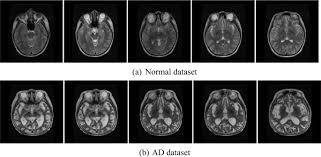

Craniotomy procedures are conducted with the help of magnetic resonance imaging (mri) scans to reach the location precisely in the brain that requires treatment. Mri stands for magnetic resonance imaging which is a technology that uses magnetic signals to show the different tissues inside the body allowing a digital image of inside the human body to be created. Magnetic resonance imaging uses a magnetic field and radio waves to create images of the body. Common questions and answers about mri scan in malaysia. The capital kuala lumpur also pulls in huge numbers of working expats looking for.

The mri machines use in neuroscience research to generate the mri machines use in neuroscience research to generate fmri images are higher resolution (via larger magnetic field strength) and cost.

Any dyes or contrasts needed during the scan will also. I called them and they patiently explained that it had cost ten thousand dollars before they got to it. I thought my insurance had denied the claim or something. Magnetic resonance imaging uses a magnetic field and radio waves to create images of the body. Mri's are primarily used to study nerves, muscles, ligaments, bones, and numerous other. Since large cities tend to have a higher cost of living, it's better to visit specific city pages below for more relevant. Images in a cardiac mri can be still or moving. Undergoing a magnetic resonance imaging (mri) scan can be a daunting experience, but this painless test is an important diagnostic tool used to help investigate a wide range of conditions and ailments that can be, depending on the circumstances, covered by both medicare or health insurance. Additional costs associated with an mri purchase. The cost of an mri scan varies per location, what hospital or clinic it is done in and what part of the anatomy is scanned. Mri scan cost in various indian cities we have mri scan price information in 89 cities. Mri cost in the same city can vary by hundreds of dollars per clinic. Craniotomy procedures are conducted with the help of magnetic resonance imaging (mri) scans to reach the location precisely in the brain that requires treatment.